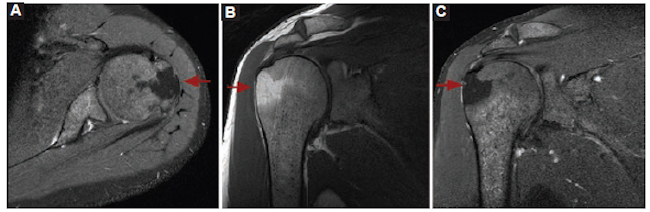

Mujer de 18 años con omalgia derecha postraumática de meses de evolución. En la Rx de hombro derecho se informó una dudosa imagen radiolúcida en el troquín, de características indeterminadas. En el centellograma óseo se observaron dos focos de hipercaptación, uno epifisario y otro en la apófisis coracoides. El informe de resonancia magnética (RM) sugirió una lesión traumática, pero no descartó otro origen. Ante la duda diagnóstica, se procedió a realizar una biopsia bajo TC (Fig. 2).

El resultado anatomopatológico informó cambios reparativos. La conclusión diagnóstica fue lesión por estrés.